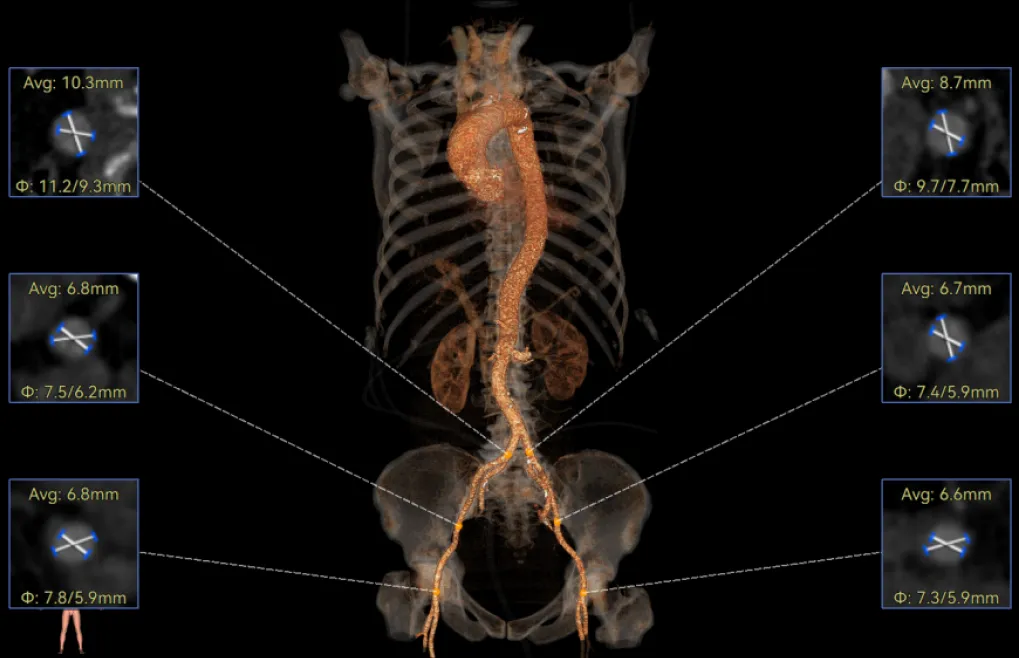

罗建方教授 广东省人民医院(点击查看专家详细简历) 设计本为临床需,耐久守护好芳华:任何医疗产品的设计初衷与最终归宿,都应落在 “临床获益” 这一核心上。尤其在 TAVR 领域,年轻患者预期寿命长,术后瓣膜的长期性能直接关乎其生活质量与生存预后。瓣膜耐久性问题,是落到临床实践中亟待突破的关键课题。传统瓣膜在长期使用中,可能因结构老化、功能退化等问题,难以满足年轻群体数十年的健康需求,二次手术风险也随之攀升。因此,产品设计必须直面这一临床痛点:通过材料革新增强抗钙化性能及生物相容性,以技术突破延长瓣膜有效使用寿命。此次临床应用的预装干瓣Prostyle A®是TAVR领域的革新理念,干瓣预期会为临床提供更耐久性的保障,实现了与临床需求的精准对接,为年轻群体的瓣膜治疗提供更坚实的保障。 李捷教授 广东省人民医院(点击查看专家详细简历) 干瓣技术求革新,性能兼顾护临床:干瓣的技术革新在创新的同时需要和临床实际需求深度耦合,兼顾TAVR术中的核心考量点。临床操作中,瓣膜能否顺利过弓,直接影响手术效率与安全性。Prostyle A®短瓣架设计及第二台阶的柔顺设计,术中操作丝滑;同时,瓣膜植入后的径向支撑力必须平衡得当,才能实现稳定锚定;释放后造影显示:瓣膜形态舒展,轻度瓣周漏,舒张压升高,冠脉开口未受影响;瓣周漏是影响术后效果的关键隐患,双层裙边设计通过多重密封机制降低反流风险,为患者长期获益筑牢防线。这些性能的协同优化,最终目的是让干瓣在临床中真正做到 “好用、耐用、安全用”,为患者预后提升提供坚实支撑。 患者病史 患者因 “活动后气促伴头晕 2 月” 入院。 现病史:2月前无诱因出现活动后气促,休息后缓解,伴头晕,夜间阵发性呼吸困难。超声检查发现:主动脉瓣重度狭窄并重度返流(跨瓣流速 4.3m/s,峰值压差 73mmHg);主动脉 + 冠状动脉 CTA 提示主动脉瓣显著钙化,升主动脉及分支粥样硬化,冠状动脉轻度狭窄(RCA 狭窄 30-40%)。 既往史:高血压病史 15 年,规律服药,血压控制稳定。 术前诊断:非风湿性主动脉瓣狭窄伴关闭不全(重度)、心功能 II 级(NYHA)、高血压病 2 级(高危)、冠状动脉粥样硬化。 术前CT 三叶瓣,瓣叶增厚中度钙化,右无交界钙化粘连,瓣环径25.1mm,LVOT 25.1mm,直筒型结构;窦部空间足够,升主未见增宽,瓣环水平夹角55°;冠脉开口位置佳,无冠脉风险;入路散在钙化、外周双侧入路无明显迂曲,双侧内径可、中分叉,左右侧均能够支持20F 大鞘通过。 造影角度及入路 右窦居中位RAO 5° CAU 26° 左冠切线位LAO 11° CRA 12° 手术策略 右侧股动脉为主入路,左侧为辅助入路;使用20球囊预扩,准备AV26瓣膜,冲洗口朝向3点钟方向送入输送系统性能,初始定位真实瓣环0位释放,最终锚定约瓣下3mm,工作位评估瓣膜稳定性与冠脉情况。 手术过程 根部造影 20mm 球囊预扩无明显腰征 术中使用26号瓣膜,瓣膜释放贴边迅速 80% 工作位观察瓣膜位置良好 释放后造影显示:瓣膜形态舒展,轻度瓣周漏,舒张压由术前30mmHg升为 60mmHg,冠脉开口未受影响。 术后超声:跨瓣流速降至1.6m/s,平均压差降至5 mmHg,心功能显著改善。 Prostyle A®预装干瓣——助力临床最优化解决方案: 1. 抗钙化与耐久性:Micro-EX™专利技术提升瓣膜抗钙化能力,适配患者瓣叶中度钙化的解剖特点,为长期疗效提供保障。 2. 柔顺过弓与精准定位:短瓣架设计 + 远端超滑涂层,确保患者输送系统过弓顺畅;瓣架流入端微直筒设计,让定位贴边更迅速,减少了手术时间; 3. 80% 可回收设计:便于术中调整观察,减少起搏时间,从而减少并发症。 4. 简化手术流程:预装设计缩短操作时间,20F 大鞘兼容外周入路,降低血管损伤风险。